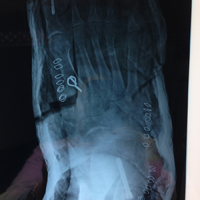

Προεγχειρητική